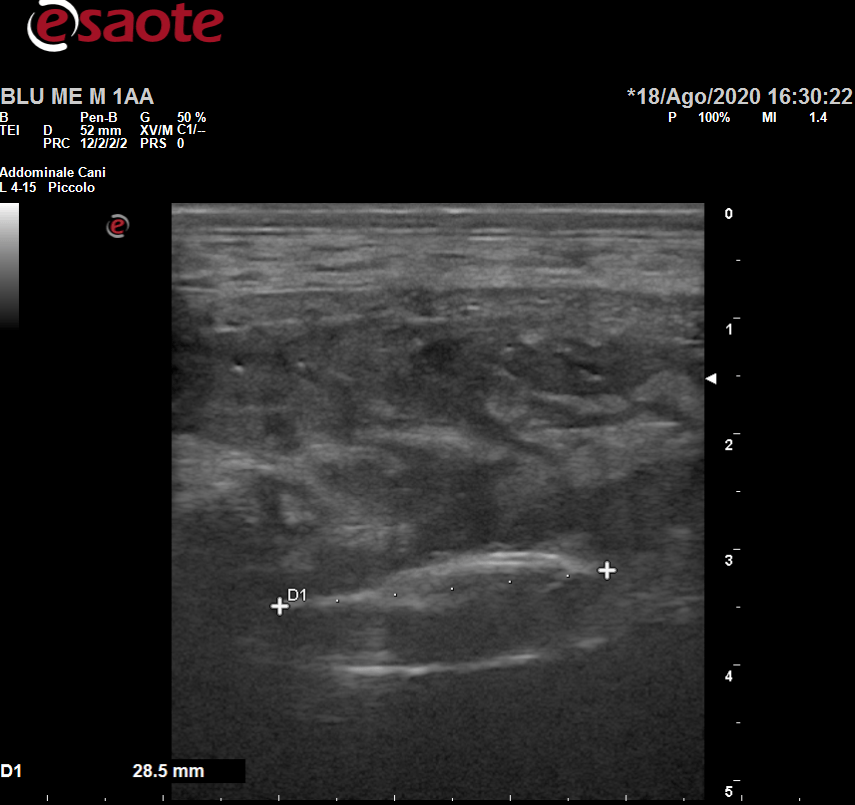

Effettuate tramite l’ecografo italiano Esaote My LabOmega, ecco quali sono le ecografie di cui ci occupiamo:

- ecografie muscolo tendinee;